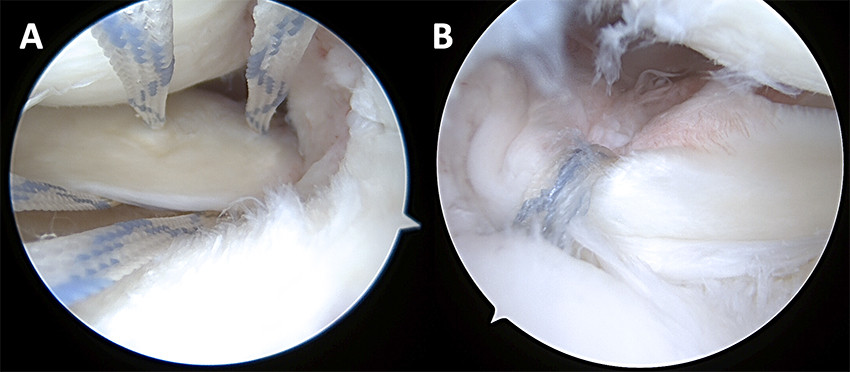

Traumatiske menisk- og rotrupturer opereres artroskopisk med reponering av menisken og fiksasjon med diverse typer suturer o.l. (figur 4). Degenerative rotrupturer opereres hvis det ikke foreligger uttalte artroseforandringer på leddbrusken. Postoperative rehabiliteringsprotokoller divergerer avhengig av type ruptur og reparasjon, men en tommelfingerregel er vektavlastning med krykker i seks uker og fysioterapiveiledet styrketrening. Huksitting er tillatt etter tre måneder, og man kan returnere til idrett og aktiviteter etter 5–7 måneder (29). I litteraturen er det beskrevet varierende grad av tilheling, men en metaanalyse av bøttehankrupturer viste 77 % tilheling (30). Ved rotrupturer er det vist opptil 93 % tilheling etter to år (31).

Å bevare en funksjonell menisk er viktig for å motvirke utvikling av degenerasjon i leddet (32). Dette anses spesielt viktig hos yngre pasienter med traumatiske rupturer (33). En metaanalyse av randomiserte kontrollerte studier viste dårligere langtidsrapporterte utfallsmål og lavere aktivitetsnivå hos pasienter med traumatiske rupturer behandlet med reseksjoner enn hos pasienter behandlet med reparasjoner (34). I tillegg er risikoen for artrose betydelig ved reseksjon, minst fem ganger økt 16 år etter meniskreseksjon (17). Risikoen er størst ved store reseksjoner (18).